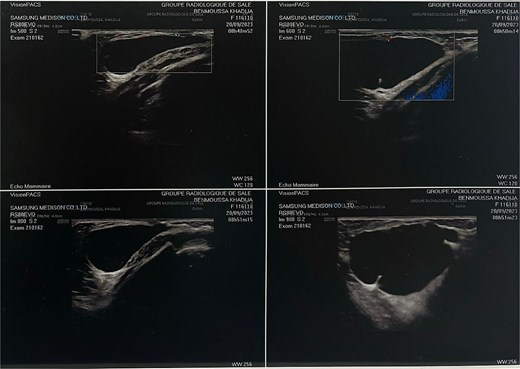

On physical examination, a soft and spongy mass was palpable in the left breast (Fig. 1). A breast ultrasound was performed, revealing an oblong, well-defined cystic mass with regular contours, an anechoic content containing fine mobile echogenic echoes, and a few thin, incomplete septa, measuring 37 × 46 mm (Fig. 2). The ultrasound concluded to a cystic breast mass, most likely a galactocele. A hormonal workup including prolactin, luteinising hormone, follicle-stimulating hormone, and estradiol was performed, with all values within the normal range.